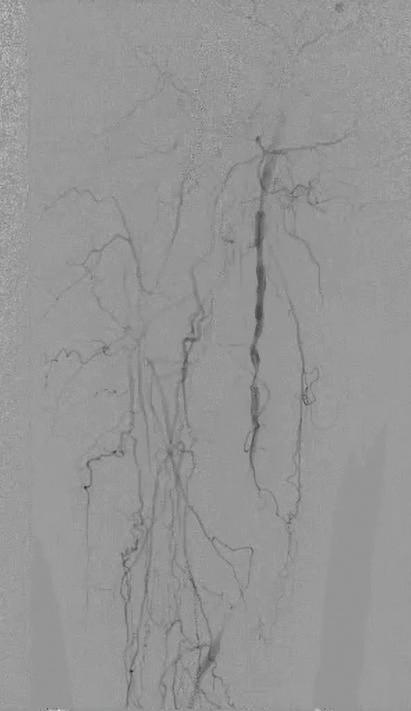

Embolization is often not very familiar to vascular surgeons. With the exception of type II endoleaks, these cases often get referred to interventional radiology (IR). As a result, there is little—if any—exposure to these procedures in vascular training. Once in practice, we don’t really think about them, despite the fact that they fit nicely into an outpatient practice.

At the hospital my practice covers, there is not much of an IR presence, so vascular surgery provides the emergency embolization services. Between the cold legs and ruptured aneurysms, we are also handling the gastrointestinal bleeds, ruptured spleens and postpartum hemorrhages. This has resulted in increasing comfort with these procedures. The anatomy and technical details are not dissimilar to what we do on a daily basis.

In addition to the hospital practice, we also have a busy office-based lab (OBL). In the context of this setting, we were asked by a gynecologist in the area about providing uterine artery embolization (UAE) for fibroids. Given our exposure to embolization procedures in the inpatient setting for emergencies, this felt like a very reasonable extension of our outpatient practice.

UAE has several characteristics that make it an ideal procedure for the outpatient setting. It is purely elective, which makes it practical to schedule. The patients are generally younger and lower risk than the typical vascular patient. The procedure itself is also low risk, with only relatively small sheaths required and the option for radial access. UAE also tends to be fairly routine and predictable. In a

involve gaining familiarity with the branch anatomy of the internal iliac artery and with embolization agents. In UAE, microparticles or liquid agents are often used. Comfort with radial access— less often used in vascular procedures— is helpful. Finally, relationships with gynecologists need to be developed, as they make these treatment decisions and referrals.

There are other elective embolization procedures that can be explored. While we’ve had minimal experience with it, prostate artery embolization is also well suited to the outpatient setting. Geniculate artery embolization is a newer procedure that has shown promise for patients with osteoarthritis who are not surgical candidates. Overall, when done well and with input from the relevant specialists, these are excellent procedures to expand an outpatient vascular practice.